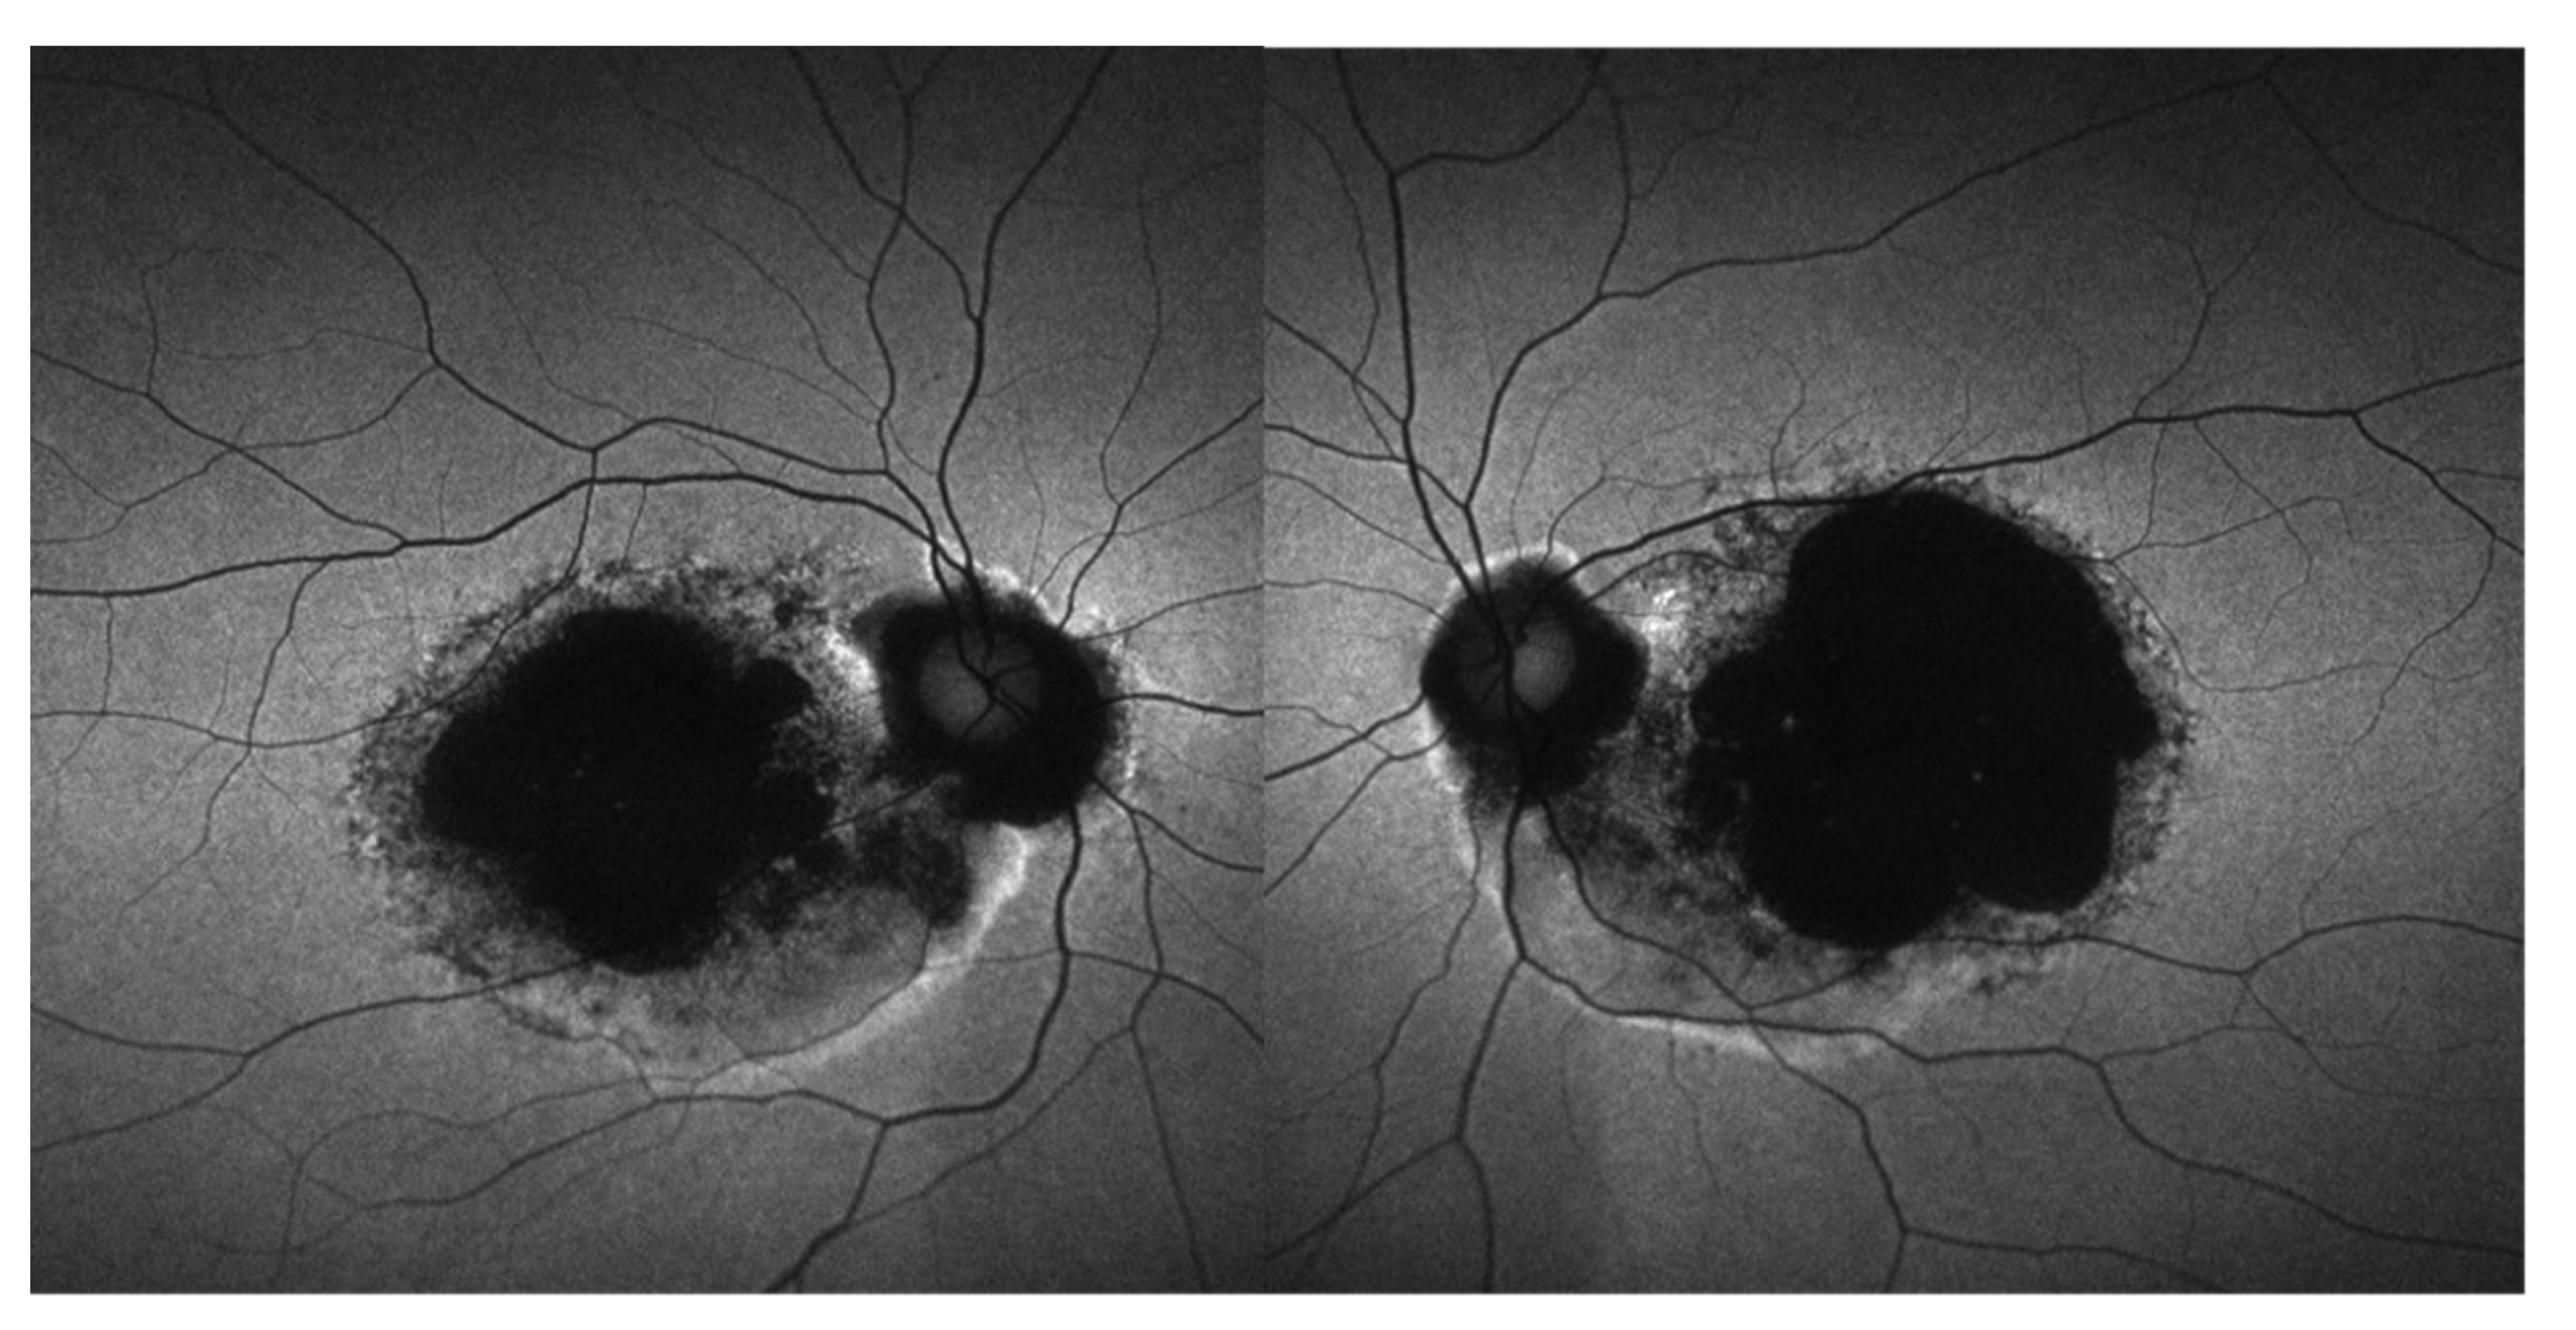

3.5. Retinal Imaging

3.7. Molecular Modeling